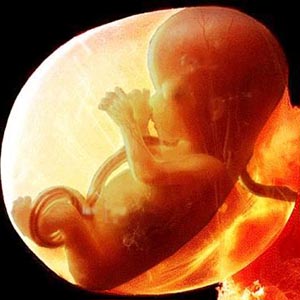

L'enfant entier a maintenant la taille de la chaux. La longueur du corps est de 44 à 60 mm et le poids est d'environ 8 g.

Tous les organes et systèmes de l'enfant sont déjà formés. Ils sont dans un état différent. Par exemple, un petit cœur bat longtemps et complètement. Mais il n'y a pas encore de squelette, le tissu osseux reste au stade cartilagineux. Jusqu'à présent, seuls les globules rouges (globules rouges) sont contenus dans le sang et les globules blancs se forment plus tard. Mais les cordes vocales se sont presque développées, bien que le bébé n'en aura pas besoin bientôt.

Voici à quoi ressemble le fœtus à la semaine 11 (cliquable):